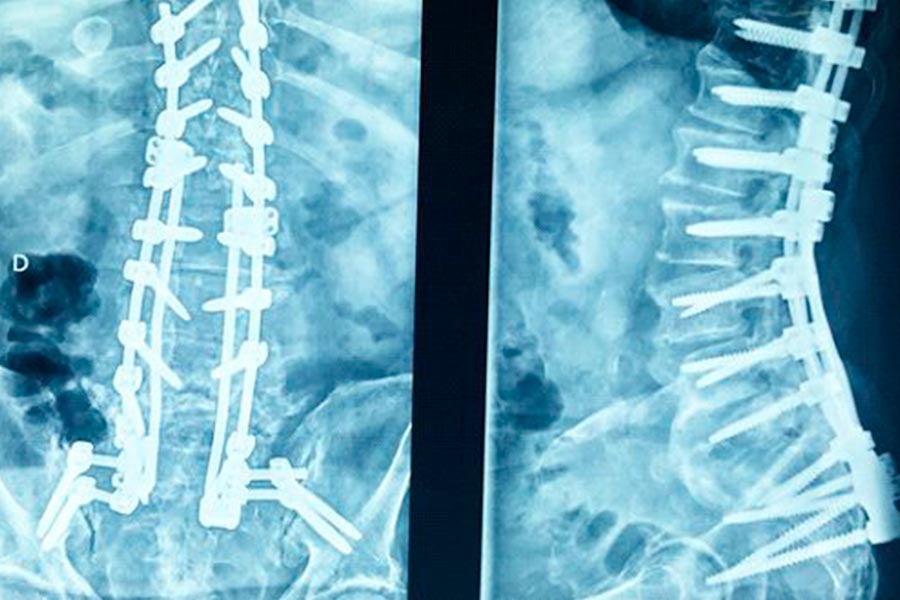

Caso clínico: endoscopia de columna multinivel L4L5 y L5S1

Los síntomas que presentaba el paciente eran dolores acentuados en las piernas, claudicación a la marcha y calambres y hormigueos en las piernas.

Durante la intervención quirúrgica, se abordarán los dos niveles mediante la técnica de endoscopia de columna.